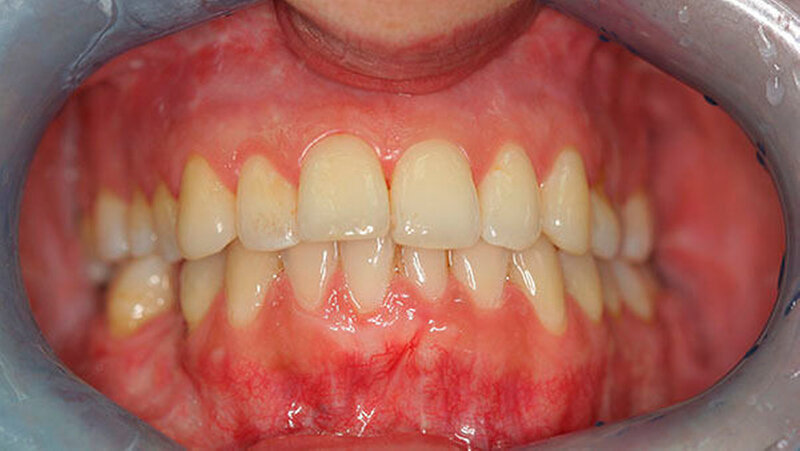

Durch diese hoch anspruchsvollen Verfahren ließ sich annähernd die ursprüngliche Position des Unterkiefers vor der Einschmelzung wiederherstellen; in der gleichen Operation wurde die Position des Oberkiefers der jetzt idealen Stellung des Unterkiefers angepasst.

Die Patientin erreicht dauerhaft eine Mundöffnung von 35 mm ohne Schmerzen, kann jede Nahrung zu sich nehmen und hat einen stabilen Zusammenbiss der Zähne - auch die erhebliche Rücklage des Unterkiefers ist dauerhaft beseitigt.